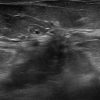

Ung thư vú

Ung thư vú - Ảnh 4

» Thông tin: Nữ giới – 50 tuổi.

» Lâm sàng: Khối tuyến vú.